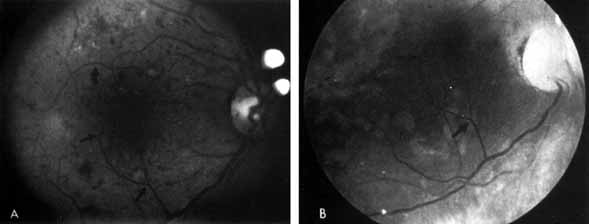

In advanced NPDR, signs of increasing retinal hypoxia appear, including multiple retinal hemorrhages, cotton-wool spots (Fig. 7), venous beading and loops (Figs. 7 and 8), intraretinal microvascular abnormalities (IRMA) (see Figs. 7 and 8), and large areas of capillary nonperfusion.

Fig. 7 A. Severe nonproliferative retinopathy with venous dilatation and beading, soft exudates, and intraretinal microvascular abnormalities B. The midphase of the angiogram shows the intraretinal microvascular abnormalities (IRMA) and severe capillary nonperfusion.

Fig. 8 Venous loop (large arrow) and intraretinal microvascular abnormalities (IRMA; small arrow).

Venous beading (see Fig. 7) and venous loops (see Fig. 8) indicates sluggish retinal circulation and are nearly always adjacent to extensive areas of capillary nonperfusion. Focal vitreous traction is thought to contribute to their formation.9 Capillaries next to areas of nonperfusion that dilate and function as collaterals are referred to as IRMA. They are frequently difficult to differentiate from surface retinal neovascularization. Fluorescein, however, does not leak from IRMA but leaks profusely from neovascularization (see Fig. 7).